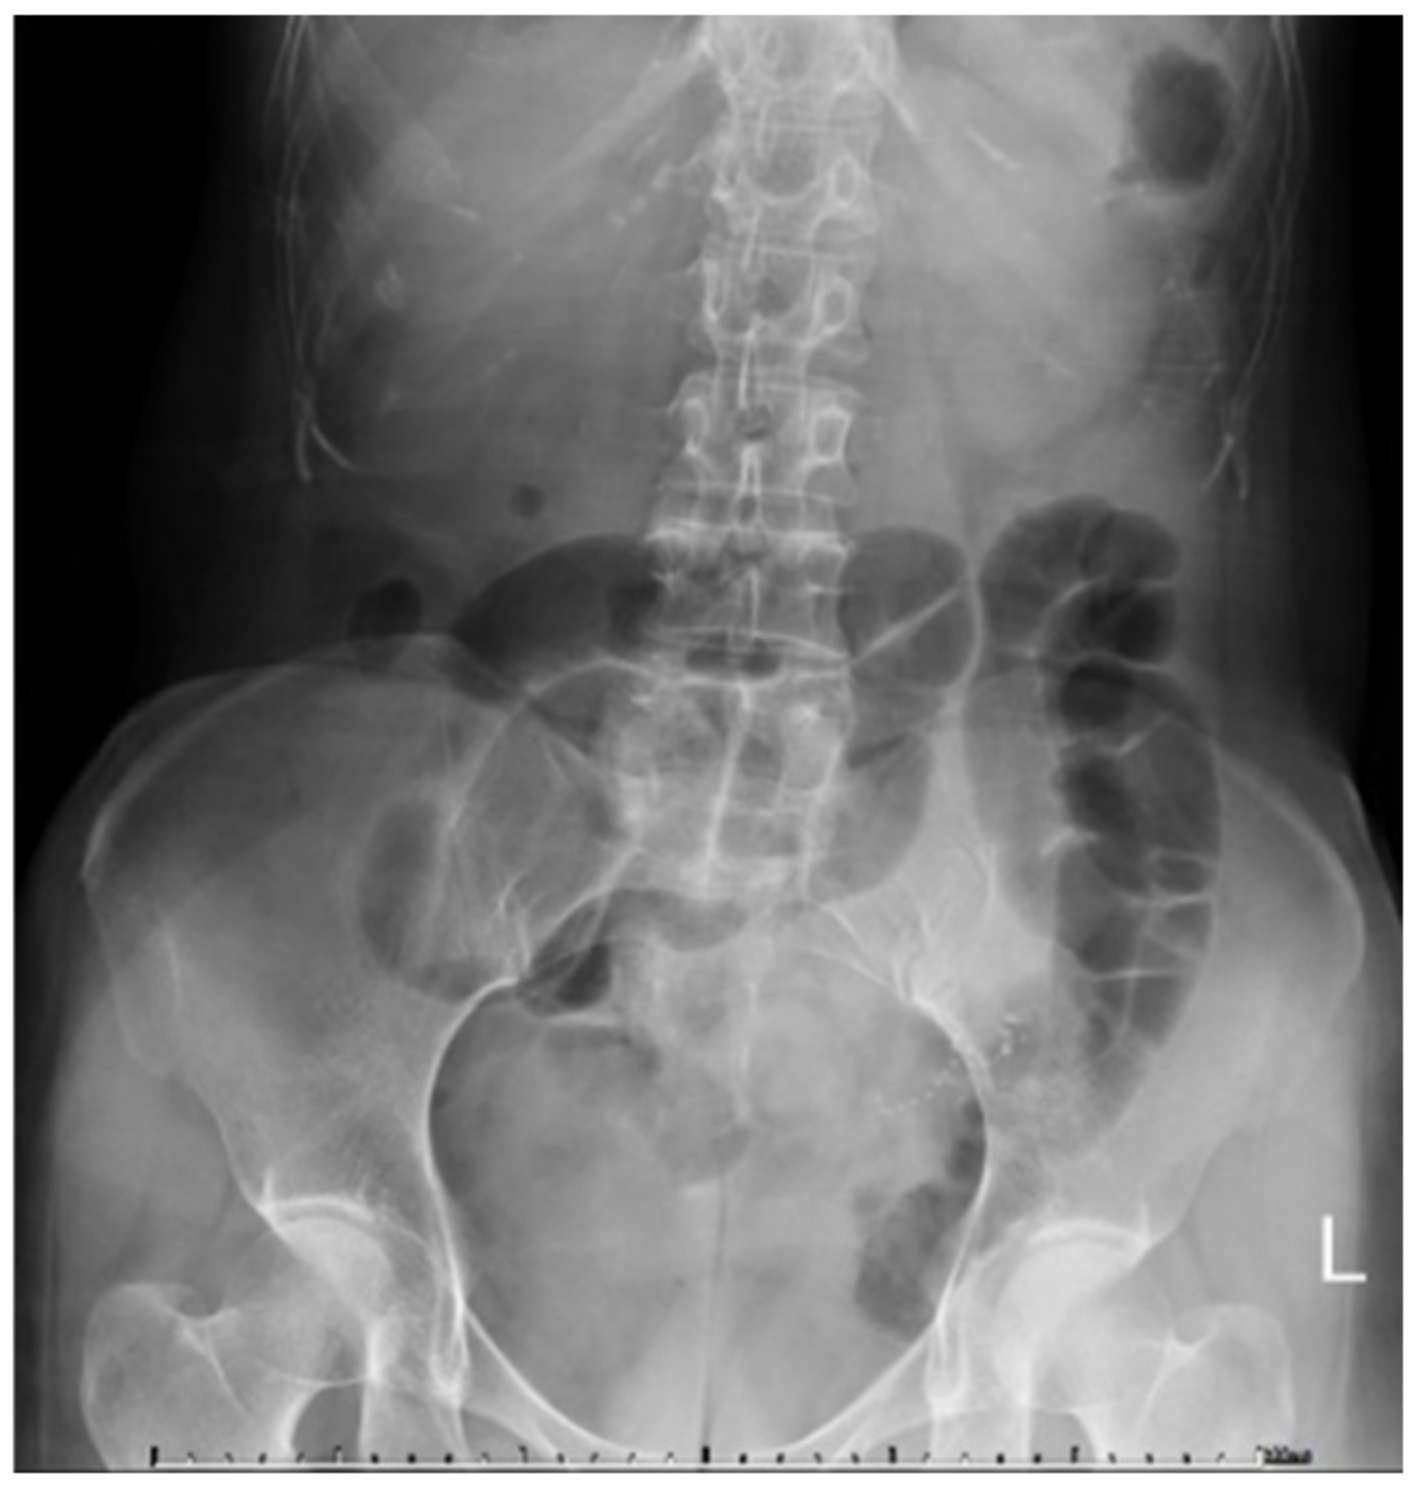

2. Case Report